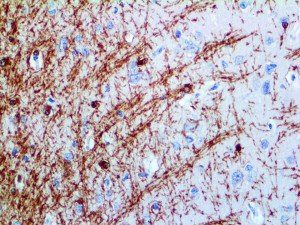

The first cytokines released are interleukin 1β (IL-1β) and tumor necrosis factor-α (TNF-α), which attract a variety of circulating white blood cells (WBCs) to the infection site, including neutrophils, monocytes, macrophages, and natural killer (NK) cells. This response, along with the antipathogenic chemicals released by these cells (i.e., complement), comprise the innate immune response. These cells directly attack the invading pathogen and also release additional cytokines, chief among them interleukin-1 and 6 (IL-6). IL-6 is essential for invoking the adaptive immune response, which calls T-cells, B-cells, and T helper (Th) cells to the infection site. IL-6 also stimulates further recruitment, proliferation and activation of macrophages.

This activation induces inflammatory monocytes to highly express IL-6, starting a localized and then systemic cascade effect that results in hyperproduction of IL-6, which accelerates the inflammatory process. Because IL-6 also increases vascular permeability, excessive levels cause blood vessels to become very leaky. This, along with clotting factors released from vascular endothelial cells, stimulates the coagulation cascade, resulting in microthrombosis (tiny clots), which leads to ischemia and tissue death of the kidney, intestines, heart, liver, brain and extremities.